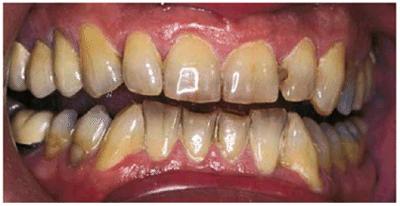

Figure 16-2A and B: Total neglect resulted in severe staining

of this patient's teeth.